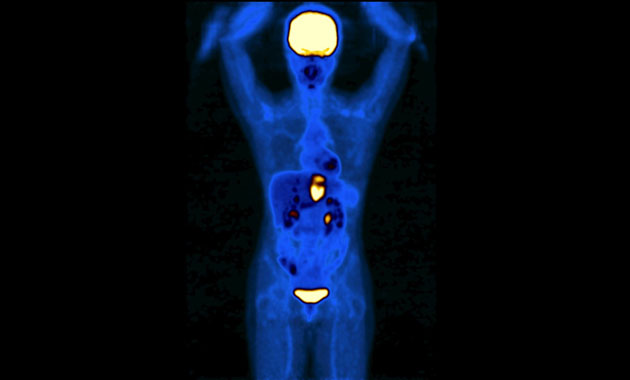

The Molecular Imaging and Therapeutics (MI&T) division, at UCSF Department of Radiology & Biomedical Imaging, oversees the clinical practice of traditional nuclear medicine, including multimodality PET/CT and PET/MR, and stewards the application of molecular therapeutic agents for our patients. The division will also work closely with the Chemistry, Probes and Molecular Therapy (CPMT) Specialized Resources Group within the department, as well as with clinicians and researchers in other departments such as oncology, cardiology and neuroscience, to usher in a new generation of imaging and treatment modalities.

- Advanced diagnostic molecular imaging modalities including new PET/CT and PET/MRI methods

- Benign and malignant tumors

- Cancers

- PET/CT